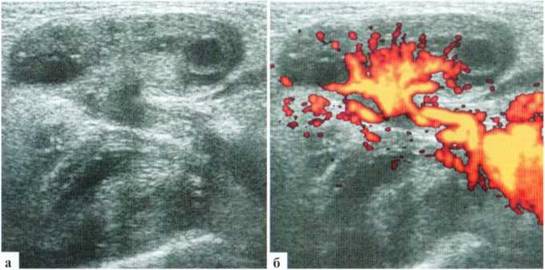

Относительно частой патологией у недоношенных девочек является паховая грыжа. В подавляющем большинстве случаев содержимым паховой грыжи у девочек является яичник, и риск возникновения его ишемических нарушений заставляет идти на оперативное лечение непосредственно по установлении диагноза. Необходимость в УЗИ возникает нечасто: для дифференциальной диагностики с воспалительными заболеваниями этой области, а также для оценки жизнеспособности яичника. При УЗИ удается достоверно визуализировать яичник, расположенный под кожей и подкожной клетчаткой, его фолликулы, место его похождения через паховый канал и сосуды, как собственно в яичнике, так и в его «ножке». Сохранение нормального строения яичника и сосудистого рисунка свидетельствует об отсутствии выраженных ишемических нарушений органа и о возможности проведения не экстренного, а срочного оперативного вмешательства (рис. 2.8). Целесообразно при УЗИ также визуализировать контралатеральный яичник, документально зафиксировать его наличие и структуру. Обычно яичник, находящийся в грыжевом мешке, несколько больше контралатерального за счет отека, даже при отсутствии гемодинамических нарушений. После операции, при сохраненной жизнеспособности яичника, эти изменения исчезают через 2—3 дня, яичники приобретают эхографически одинаковый вид.

Рис. 2.8. Паховая грыжа у новорожденной: а, б — левый яичник находится в паховой области в грыжевом мешке. Размеры — 22x13 мм, четко прослеживаются фолликулы до 5 мм в диаметре и стромальный компонент. Четко прослеживается сосудистый рисунок как в ткани яичника, так и в его «ножке», идущей через паховый канал